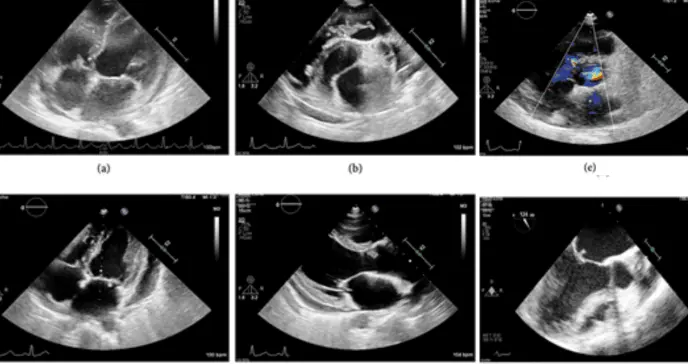

El ecocardiograma 2D fue crucial para el diagnóstico, al mostrar vegetaciones (acúmulos anormales de material infectado) en las cuatro válvulas cardíacas. Las vegetaciones más grandes se localizaban en la válvula pulmonar (tres vegetaciones de hasta 12x6 mm), seguidas de una en la cúspide coronaria derecha de la válvula aórtica (16x5 mm), otra en la válvula mitral (7x5 mm) y una en la tricúspide (8x2 mm).

Se confirmó la presencia de la CIV perimembranosa restrictiva de 3 mm. Las vegetaciones provocaban insuficiencia pulmonar grave, insuficiencia aórtica moderada, insuficiencia mitral grave e insuficiencia tricuspídea leve. Además, se observó hipocinesia global del ventrículo izquierdo con una fracción de eyección del 42%. Los estudios autoinmunes y de inmunodepresión resultaron negativos.

Tras completar un total de seis semanas de terapia antibiótica intravenosa en el hospital, la paciente experimentó una mejoría clínica significativa. Un ecocardiograma de control mostró la desaparición de la vegetación tricuspídea y la reducción de las demás a pequeños nódulos calcificados en las válvulas mitral, aórtica y pulmonar, con una mejoría en los grados de insuficiencia valvular.